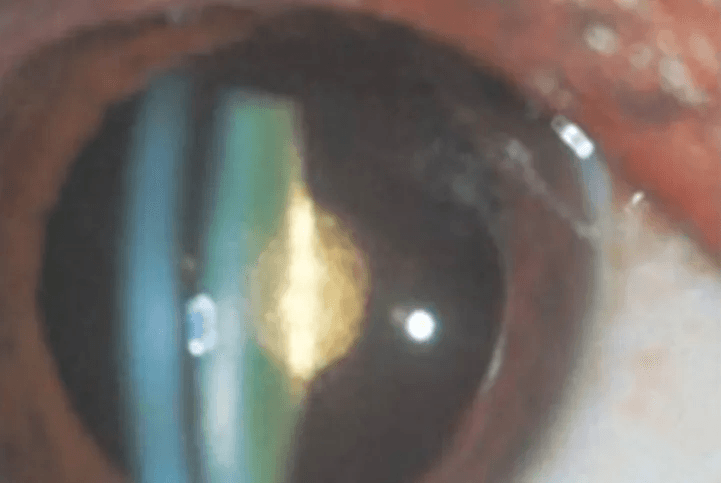

A cataract is a clouding of the eye's natural lens which impedes the passage of light,

causing a decrease in the vision. It is the most common cause of vision loss in people over

the age of 40, and is the prinicipal cause of blindness in the world.

The lens is made of mostly water and protein. The protein is arranged in a precise way that

keeps the lens clear, allowing light to pass through it to focus a clear image. As we age,

this protein begins to break down and clump together, and start to cloud a small area of the

lens which forms cataract. Over time, the cataract may become denser, making it more

difficult to see.